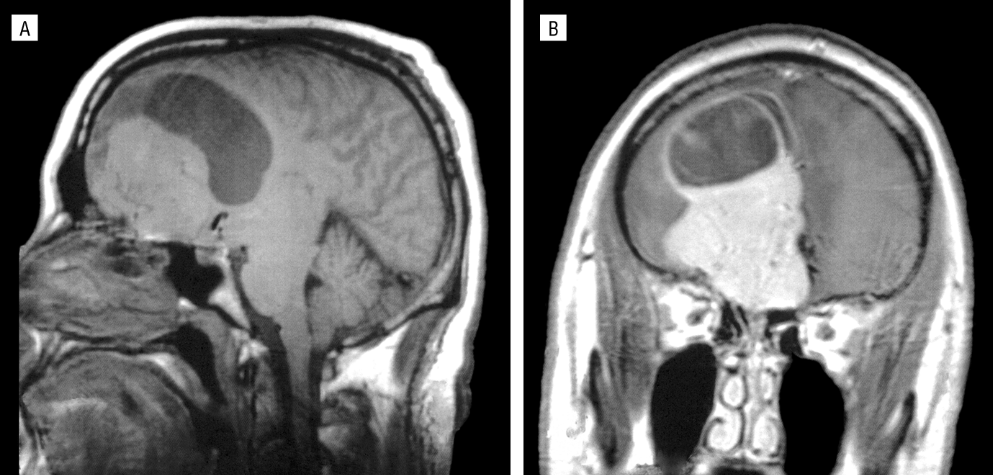

“Mr. Oft” was a schoolteacher who, despite having no psychiatric history of sexually deviant behavior, became interested in child pornography in middle age and began engaging in inappropriate behaviors towards others, including his own step-daughter. It was later discovered that he had grown a tumor on his right orbitofrontal cortex (abnormalities in this area have been associated with poor impulse control, altered sexual behavior, and sociopathy). When Mr. Oft’s tumor was removed, his pedophilia subsided; later, the tumor grew back, and the urges returned and he began secretly collecting child pornography. Again, the tumor was removed, and Mr. Oft’s urges subsided.

Image Credit: Burns JM, Swerdlow RH. Right Orbitofrontal Tumor With Pedophilia Symptom and Constructional Apraxia Sign. Arch Neurol. 2003;60(3):437–440. doi:10.1001/archneur.60.3.437